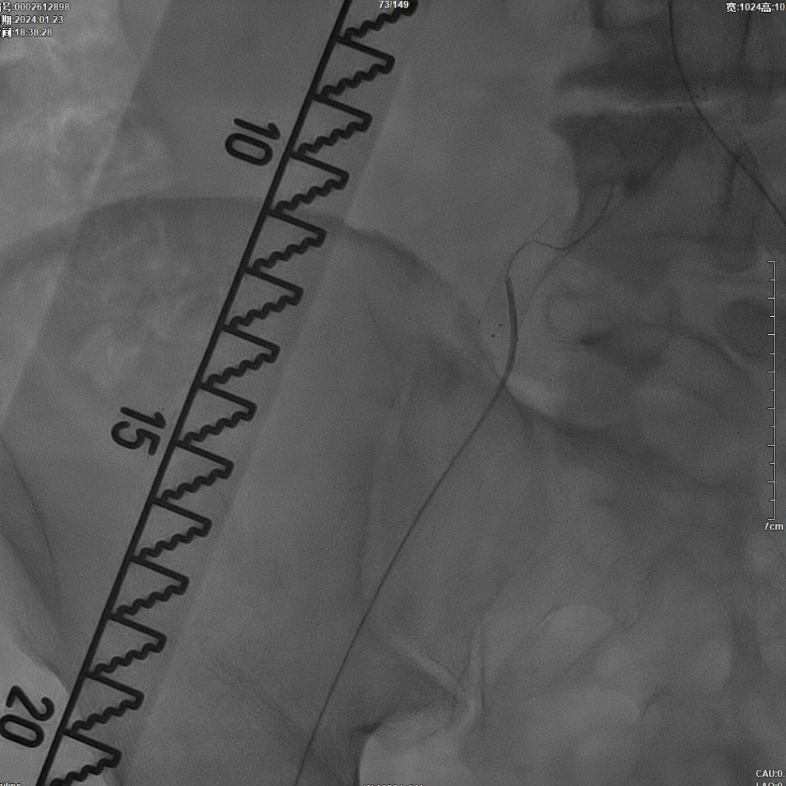

减容后造影显示仍存在重度残存狭窄,遂沿右侧股动脉置入VBX支架(直径11mm,长度59mm)。支架定位需满足近端完全覆盖腹主动脉病变段,远端距离双侧髂总动脉分叉至少1.5cm,以避免后扩张时大球囊对髂动脉造成损伤。

该图解释为何远端距离双侧髂总动脉分叉至少1.5cm,以避免后扩张时大球囊对髂动脉造成损伤。